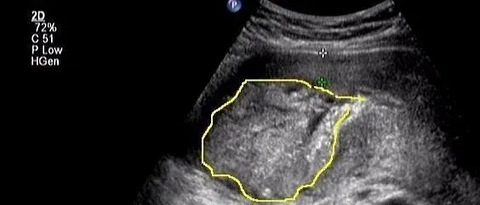

36周胎儿4.5斤左右,40周生产,最终宝宝因为重度窒息离开

看到林小暖发的,她收到一条网友的留言,真的好心痛。 她36周b超显示胎儿4.5斤左右(已经低于10%,至少也是疑似胎儿宫内生长受限fgr了),但产检医生没有给任何提示和建议,只是让她继续妊娠等生产。 40周她见红破水去医院,进待产室。凌晨胎心监护显示胎心不时下降到60-80,护士进来让侧躺吸氧,继续试产,随后离开。接下来俩小时没有人再来询问,直到俩小时后她觉得宫缩太强太疼了叫来护士,护士已经测不到